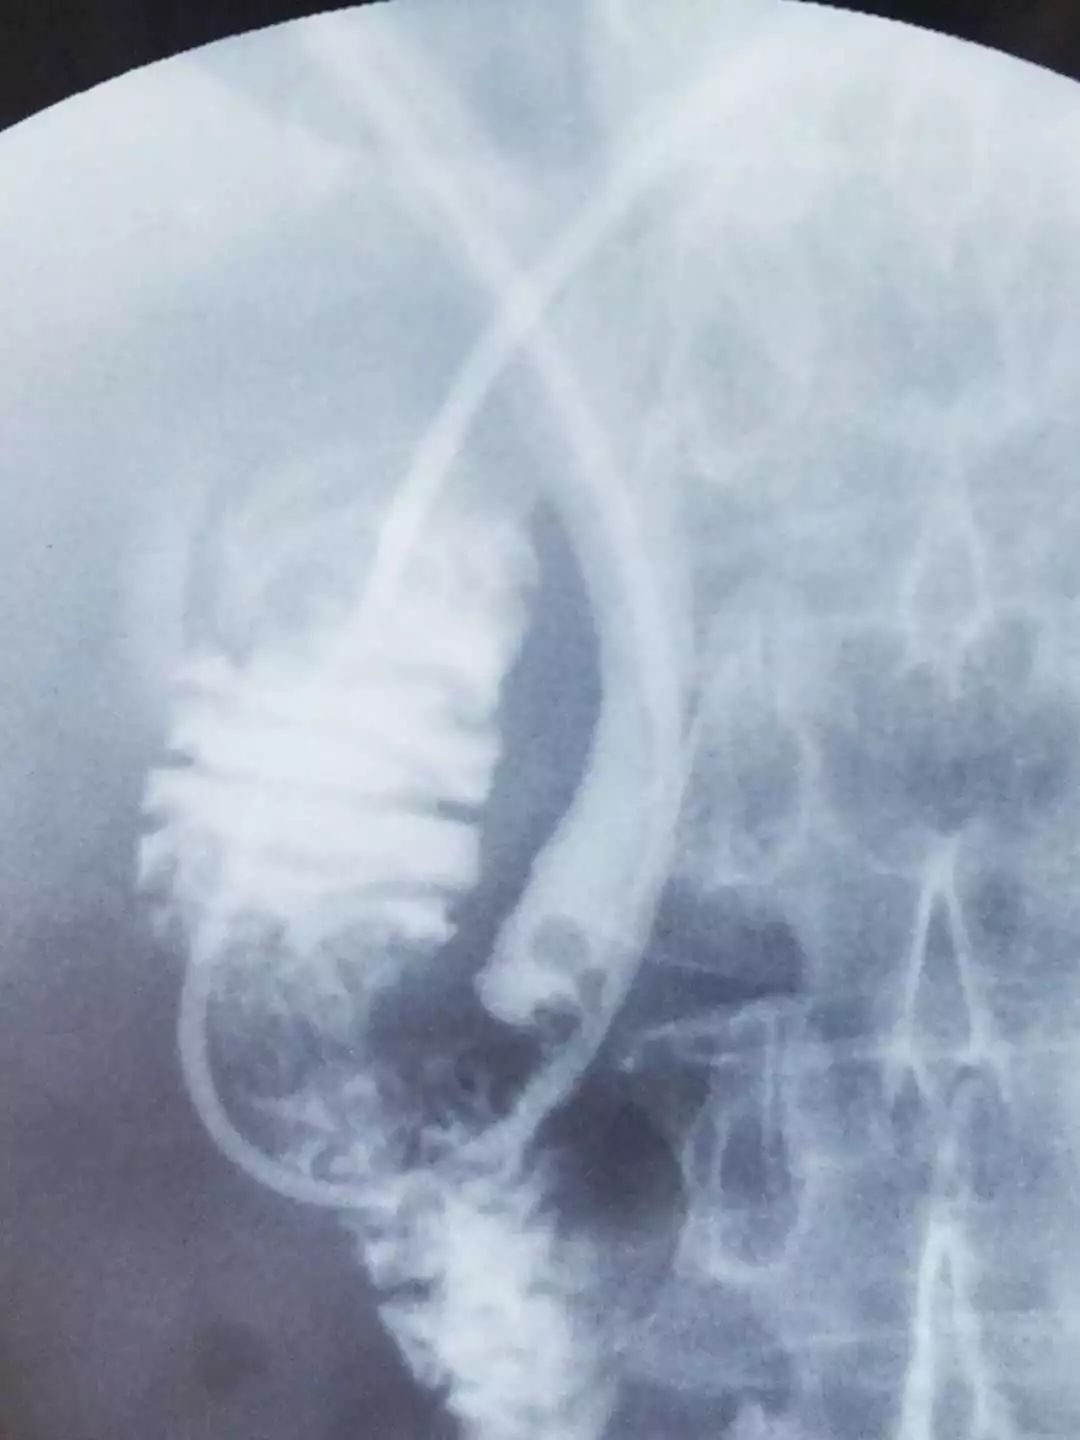

三、经内镜逆行胰胆管造影(ERCP)

胆胰疾病为常见消化系统疾患之一,近年来,随着内镜技术的不断发展,经内镜逆行胰胆管造影(ERCP)诊断技术及十二指肠乳头括约肌切开(EST)治疗技术,已成为肝、胆、胰疾病诊断和治疗的重要手段,并已部分取代外科手术治疗,具有疗效满意,创伤少,不良反应小,患者乐意接受等优势。